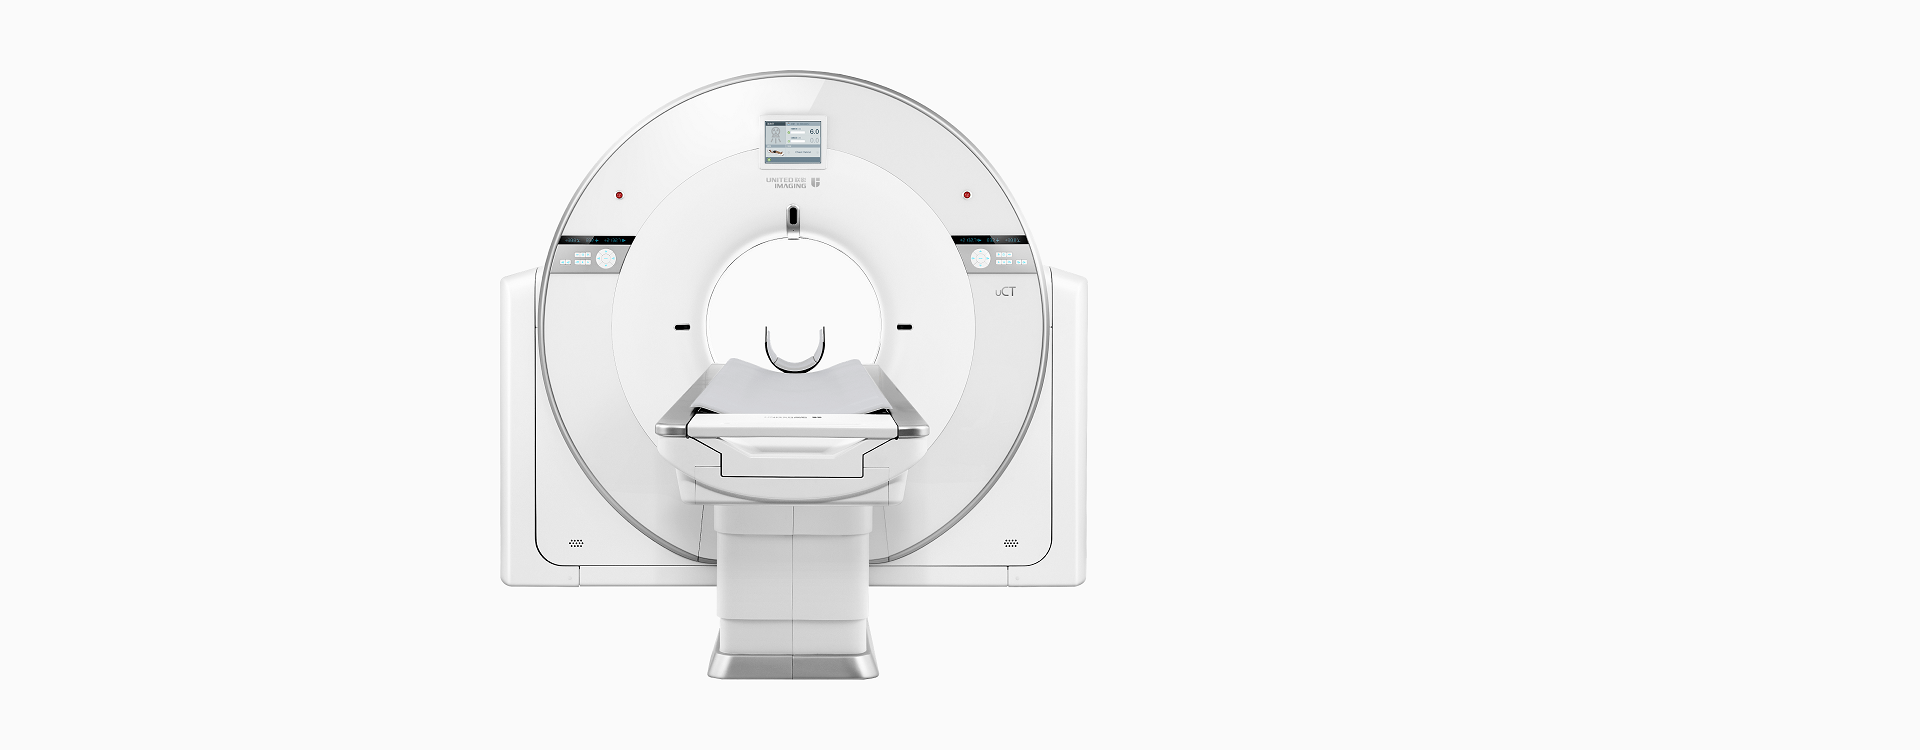

心有乾坤

乾坤CT集40排时空探测器、KARL 3D®迭代重建技术、智能管家平台等高端软硬件于一身,实现图像精度、低剂量与扫描速度的三重突破,还原影像细节,提升35%的扫描启动时间,提供可媲美64排CT的临床效能。

时空平台

高端硬件

40排时空探测器

22mm覆盖,0.55mm层厚,卓越空间分辨率与密度分辨率兼而得之